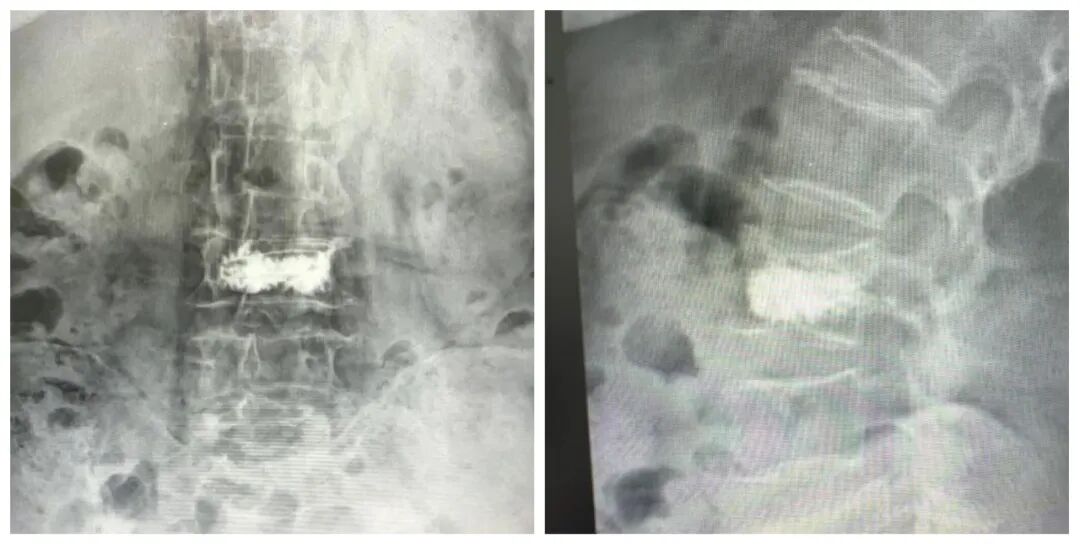

面对家属“希望老人尽快摆脱疼痛、重新站起来”的迫切愿望,骨科主任高胜一迅速组织多学科会诊。团队结合患者影像学检查结果、全身状况综合评估,在充分与家属沟通手术风险与预期获益后,最终确定采用经皮椎体后凸成形术(PKP)方案。该手术具有创伤小、恢复快的优势,通过背部小切口,在影像设备精准定位下插入球囊扩张器恢复椎体高度,再注入骨水泥稳定椎体结构,可有效缓解疼痛并避免长期卧床并发症。

经详细术前评估与充分准备,手术当日,高胜一与副主任医师杨兆平紧密配合,顺利穿刺并注入骨水泥,整个操作过程精细流畅,耗时约30分钟。王奶奶麻醉苏醒后,便明显感觉到折磨多日的腰背剧痛大幅减轻。次日,在医护人员指导下,老人顺利下床行走,有效避免了长期卧床可能引发的各类并发症。看着老人重新露出的笑容,家属悬着的心终于落了地。目前王奶奶已顺利康复出院,回归正常的家庭生活。